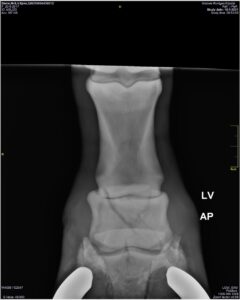

‘Op 12 januari 2021 stond Dame ineens op drie benen. We dachten dat ze in de binnenbak een klap had opgelopen van een van haar paardenvriendinnen’, gaat Dieke terug naar de fatale dag. ‘De dierenarts kon niet 123 een oorzaak vinden, en adviseerde een weekje boxrust. Maar Dame wilde absoluut niet staan op linksvoor. Dit voelde voor ons niet goed en toen besloten wij om de kliniek te bellen. Foto’s met het mobiele röntgenapparaat van de dierenarts in Klijndijk op 18 januari wezen uit dat het hoef- en kroonbeen beide op zeven plaatsen gebroken waren. Het zag er dramatisch uit; onze Dame was ten dode opgeschreven …’

De familie Slingerland wilde haar niet meteen opgeven; ook omdat Dame als ze ‘gewoon’ op stal stond haar vrolijke en aanhankelijke zelf was, en dan geen tekenen van pijn vertoonde. ‘We stuurden de foto’s naar alle klinieken die we maar konden vinden; in Hannover, Den Bosch, Utrecht … niemand durfde de noodzakelijke operatie om de botjes op hun plek te krijgen, aan en ze gaven ons een overlevingskans van 10%. Na een week, op dinsdagavond, hakten we de knoop door: “Morgen bellen we de dierenarts om haar een spuitje te geven.” Diezelfde avond ontvingen we dat mailtje van dierenarts Aart Schutrups van de kliniek in Wolvega …’

‘Hij wilde Dame een kans geven, net zoals wij die haar zo graag gunden’, vervolgt Dieke haar verhaal. ‘Dame werd onder narcose gebracht om alles recht te zetten en is in het gips gezet nadat controlefoto’s hadden bevestigd dat ‘de boel’ goed aan elkaar gezet was. Zes weken lang heeft ze in Wolvega gestaan. Telkens werden er foto’s gemaakt. We hebben haar al die tijd regelmatig bezocht en elke keer was ze zo blij dat ze ons zag! Ze kwam totaal niet ongelukkig over en ging “verstandig” met haar loopgips om. Zo lag ze veel, en het lukte haar om haar geblesseerde been te ontlasten, zelfs als ze opstond. Aart liet ook weten dat hij de gok met Dame mede aandurfde omdat ze een braaf en rustig paard was.’

‘Eenmaal terug in Elim moest de merrie nog vier weken in het gips en op rust staan. Nadat Aart de laatste controlefoto’s gemaakt had, zei hij: “Nu geef ik het uit handen.” In totaal heeft hij maar liefst een half jaar lang het hele traject met Dame begeleid. Echt heel bijzonder vinden we dat, en we zijn hem er eeuwig dankbaar voor dat hij het met Dame aangedurfd heeft!’